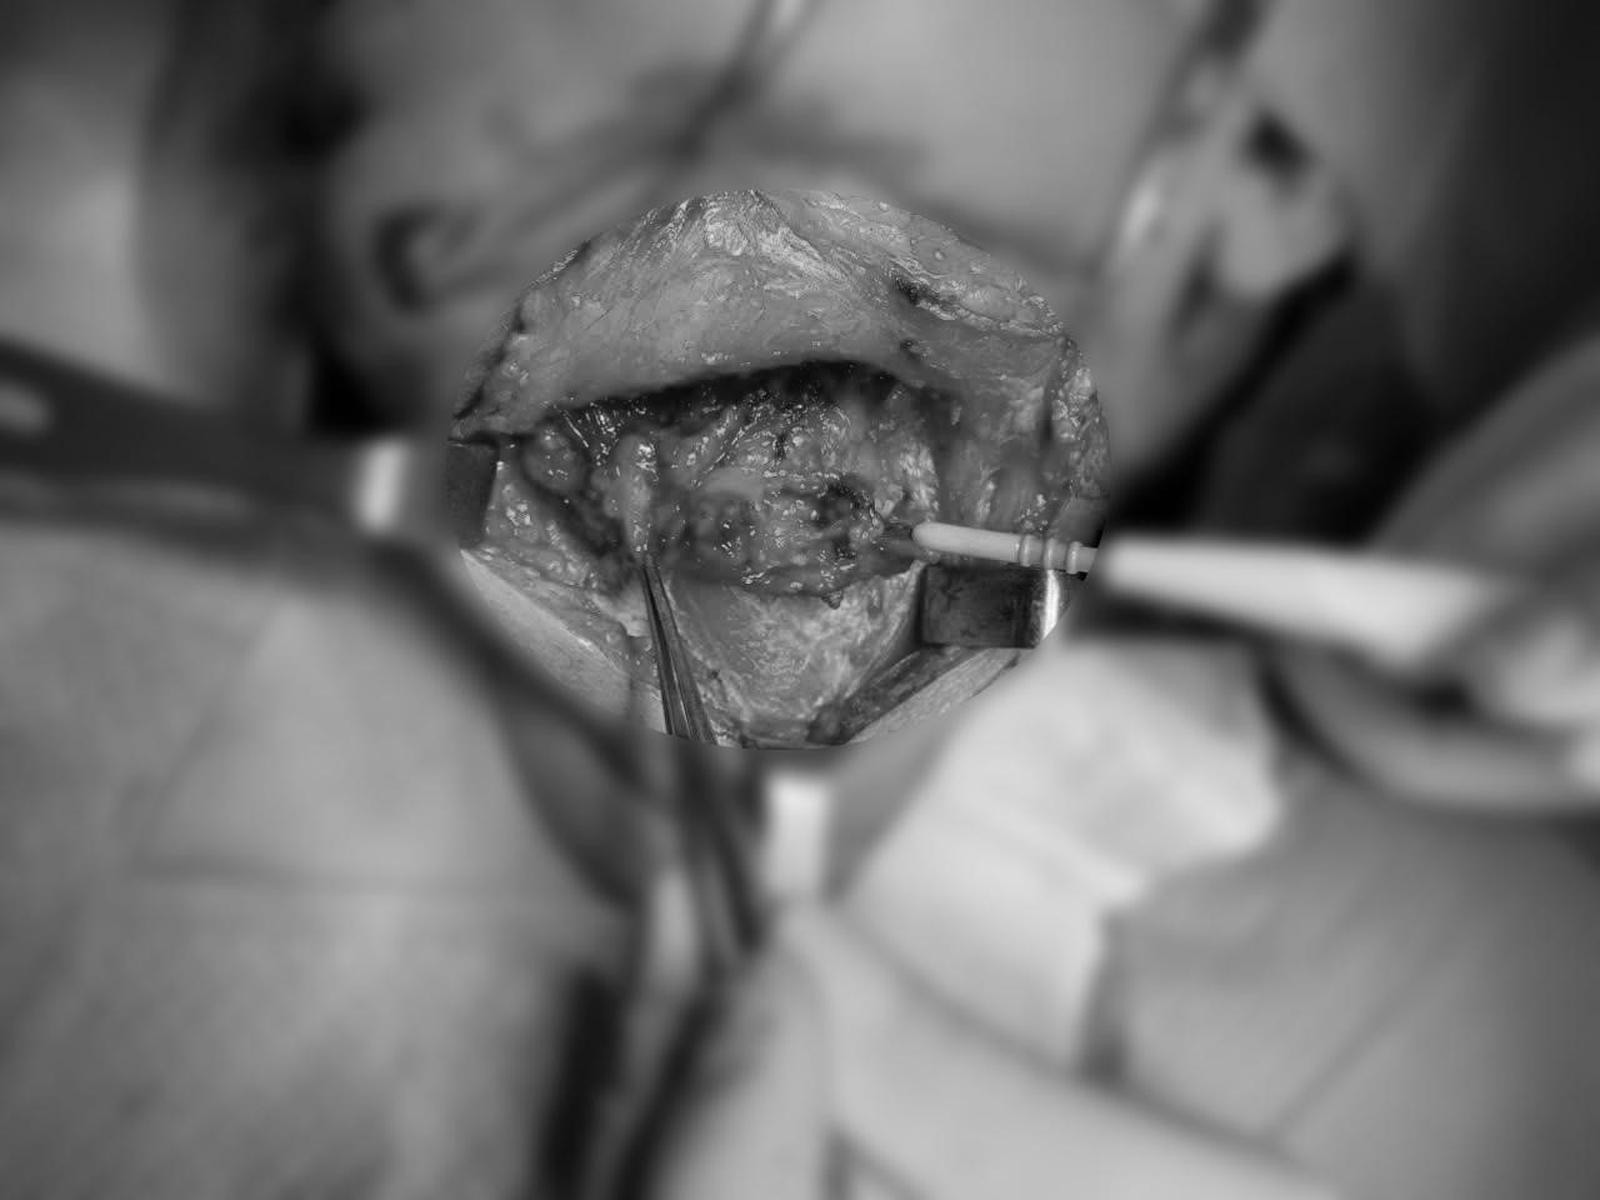

Giai đoạn 2 - Loại bỏ khối u: Ê-kíp tiến hành rạch da vùng mặt trái từ môi trên đến cạnh mũi và dưới mi mắt để tiếp cận khối u nằm sâu bên trong. Sau khi bóc tách, khối u được xác nhận đã xâm lấn nhiều cấu trúc quan trọng như xương hàm trên, xương khẩu cái, cơ chân bướm hàm và vách mũi xoang.

Khối u xoang dần lộ diện sau quá trình bóc tách của ekip Tai Mũi Họng. (Ảnh: Bệnh viện cung cấp)

“Qua đánh giá trong mổ, chúng tôi ghi nhận khối u đã lan rộng và xâm lấn nhiều cấu trúc quan trọng vùng hàm mặt. Vì vậy, ê-kíp phải cắt bỏ toàn bộ khối u cùng phần mô và xương bị ảnh hưởng, nhằm giảm nguy cơ tái phát và hạn chế tối đa tổn thương mô lành. Các mẫu khối u, bờ phẫu thuật và hạch cổ đều được gửi sinh thiết để xác định mức độ lan rộng của tế bào ung thư và đảm bảo an toàn cho người bệnh.” - BS Vinh cho biết.